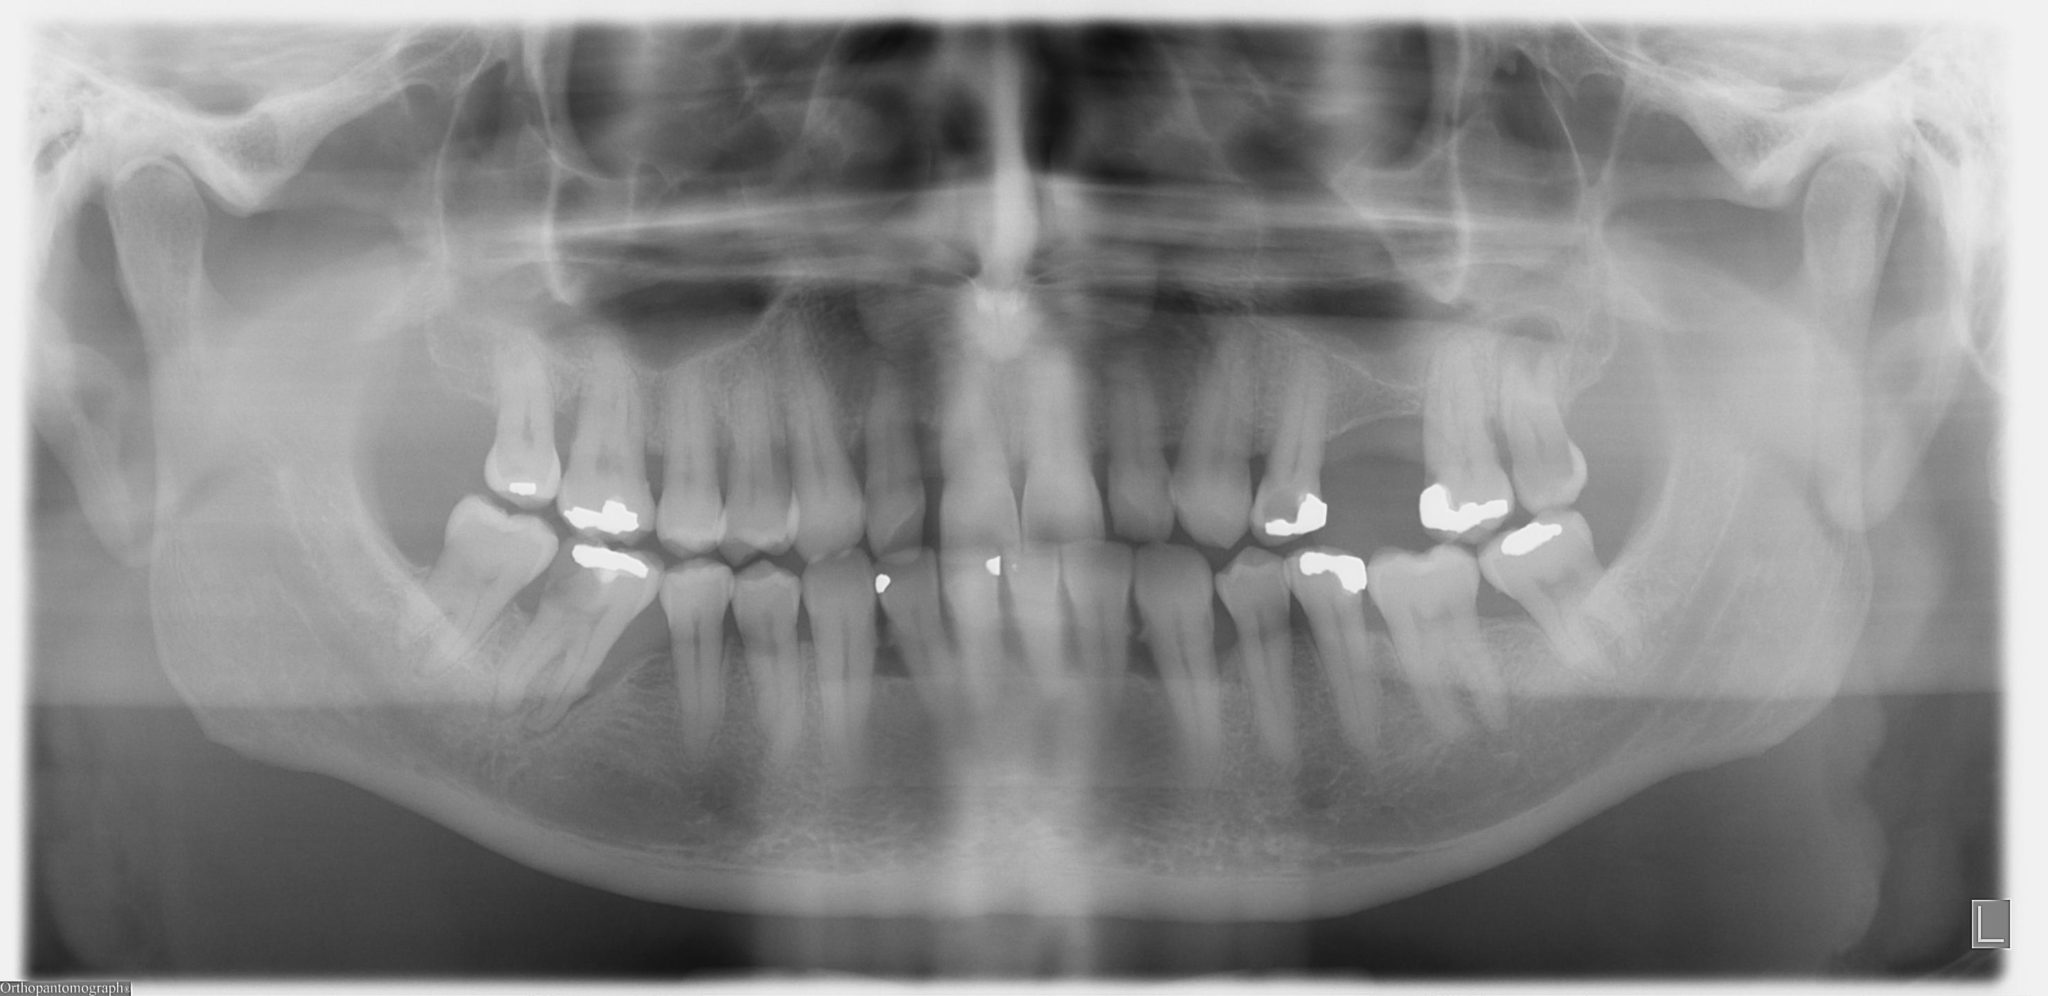

From www.sciencephoto.com

Dental sinus Stock Image C026/9215 Science Photo Library Abscess Tooth Or Sinus Infection Without proper treatment, tooth infections can spread to other areas of. A tooth abscess is a localized infection caused by bacteria within a tooth or gum, while a sinus infection occurs when the sinus cavities become inflamed and infected due to. If that happens, the infection might spread to your sinuses, open spaces in your. In fact, pain in the. Abscess Tooth Or Sinus Infection.

From radiopaedia.org

Dental abscess and maxillary sinusitis Image Abscess Tooth Or Sinus Infection Yes, a sinus infection (sinusitis) can cause a toothache. If that happens, the infection might spread to your sinuses, open spaces in your. If the abscessed tooth is near your sinus, it can create a hole between your tooth and your sinus. In fact, pain in the upper back teeth is a fairly common symptom with sinus. A tooth that. Abscess Tooth Or Sinus Infection.